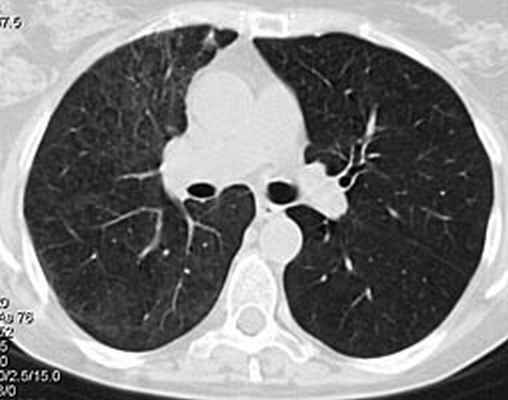

Рис 3. Биопсия легкого. Микрофото: А - альвеолы со склерозированными перегородками заполнены фибрином; Б - склероз стенок бронхов и артерий.